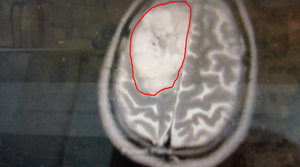

Meet my tumor

Time to cut to the chase. This is my brain tumor. There are many like it, but this one is mine. I've nicknamed him Gary Glia. Gary because it is a seemingly unpopular name nowadays in the UK (can't imagine why...), so it seemed quite appropriate. And Glia because it is the type of cell in my brain that has gone tumorous.

Gary is an unpaying tenant that has taken up residence in my head. What a prick!

A few days later I had a meeting with the neurosurgeon where I was shown the above images. Now full respect to the neurosurgeon I spoke too, I like him. He was straight down the line and straight to the point. No sugar coating, no forewarning about the size of the tumor. After 30 minutes of chatting about all of the above, he simply pulled his phone out and showed me image number 1 you see above. You could say I wasn't exactly prepared for the image, a understatement if ever there was one. But in all honesty I don't think I ever would be. So it was a good tactic. Make it quick and painless, just like ripping off a band-aid!

So, what do we know about Gary?

- He's big... look at the size of this unit. I'm amazed I can even function at all to be honest!

- He's of the type called oligodendroglioma and currently believed to be a Grade 2 (slow growing) tumor. Wondering how you pronounce that? Isn't YouTube great!

- He's very rare, with only 1,217 people diagnosed with this type in the US every year out of a population of 328 million!

- He's a number of years old. The neurosurgeon said a couple of years, but I personally suspect he could be 7 or 8 years old due to other symptoms in my past I now think could be related.

- He's a prick.